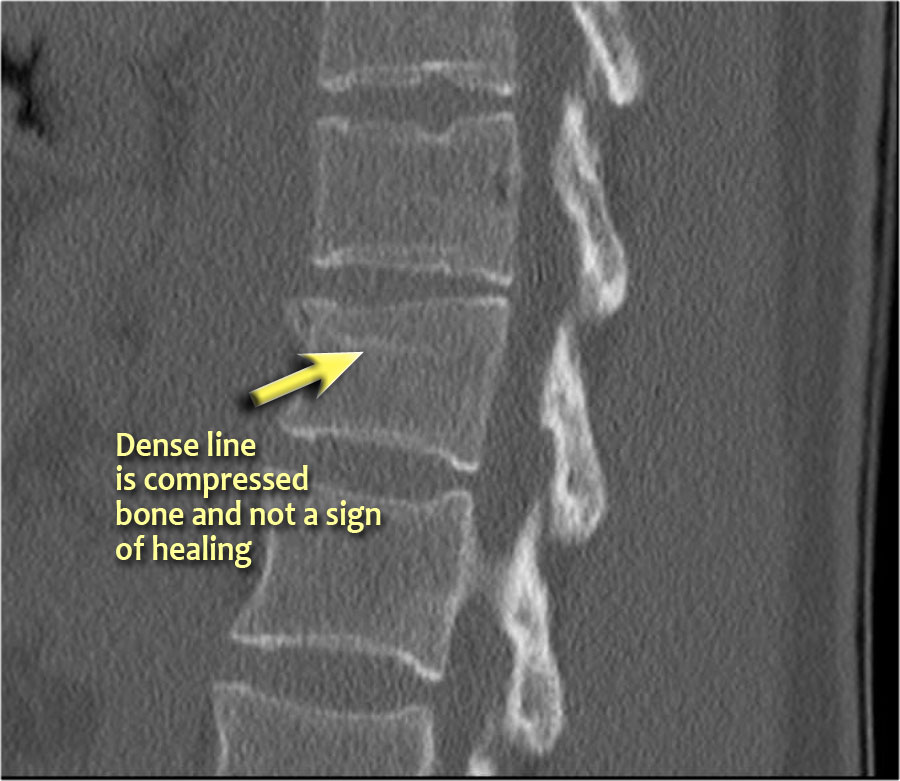

Lưu ý dải tăng tỷ trọng theo chiều ngang, thường được mô tả là xơ cứng (sclerosis).

Dải tăng tỷ trọng này không có nghĩa là tổn thương cũ đang lành với xơ cứng.

Đây đơn thuần là dấu hiệu của sự chèn ép bè xương (trabecular impaction) trong gãy xương cấp tính.